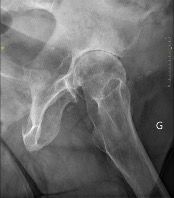

Hips in coxa vara sometimes present a very significant femoral offset which may be prove to be difficult to restore using standard stems. In this case, a varus-tilted or lateralized stem should be used and this will require a very low femoral cut, often with loss of residual femoral offset and a risk of lengthening the lower limb. Positioning a straight cementless stem in varus runs the risk of trajectory error and femoral pain. If a modular neck implant is chosen, the increased lever arm results in significant pressures on the modular neck and neck-head junction with risks that are already known. Finally, even with a cemented stem, positioning it in varus will increase the pressures on the bone-cement interface, with a risk of early loosening. With calcar-guided short stems, the stem will follow the medial cortex of the neck (which will have been cut high), naturally finding a varus tilt and making it possible to reproduce even very significant offsets (Figs 4 and 5).

While the initial goal is to restore the preoperative anatomy as closely as possible, it may have undergone changes due to fracture malunions, pathologies or surgical interventions, especially osteotomy, making it complex to open the femoral shaft. Sometimes, it is simply the native morphology of the femur that is unusual and requires technical consideration from the surgeon. It may in these cases prove very useful to choose a short stem (Figs 7 and 8). These are less common indications but they are worth mentioning.